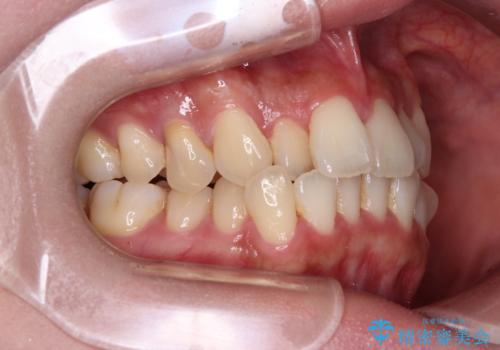

- 上下前歯のデコボコやクロスバイトを気にして来院された患者様です。

上顎歯列が下顎の歯列に対して狭小であり、一部下顎の奥歯が上顎よりも外側に位置している状態でした。

上顎の急速拡大装置を使用して上顎骨を側方に拡大することで上顎歯列を拡大し、下顎歯列も拡大できるようにすることで、歯列を整えることとしました。